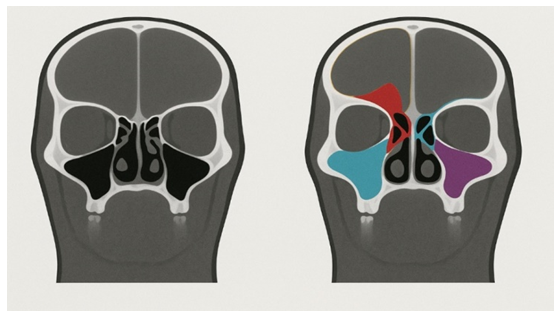

CT data from all patients were utilized not only for clinical diagnostic purposes but also to compile a comprehensive dataset of images that served as the basis for training and testing artificial intelligence algorithms. The integration of a deep learning–based system into the CT image analysis workflow for the main study group demonstrated the model’s ability to accurately detect and localize key radiologic features characteristic of each type of paranasal sinus pathology. This approach contributed to an improvement in diagnostic accuracy, reproducibility, and standardization of interpretation, while reducing the influence of subjective factors.• Frontal sinusitis (n = 36) — The AI system consistently recognized hypodense filling zones within the frontal sinuses, corresponding to mucopurulent accumulation, along with areas of mucosal thickening and obliteration of the frontonasal duct. Automatic segmentation provided clear boundaries between pathological content and normally aerated sinus cavities, ensuring precise volumetric assessment. The algorithm demonstrated particular sensitivity in detecting minimal hyperplastic changes that might be overlooked during routine visual analysis by a radiologist. Additionally, the system generated high-quality multiplanar reconstructions, allowing improved visualization of the extent of involvement and potential obstruction of drainage pathways.• Maxillary sinusitis (n = 42) — The AI algorithm showed strong performance in identifying characteristic features such as horizontal fluid levels, diffuse mucosal hyperplasia, and sclerosis of the bony sinus walls. In cases of polypoid changes, the system accurately segmented the masses, provided volumetric measurements, and differentiated them from retained secretions or mucosal thickening. Furthermore, the AI reliably detected contiguous involvement of the ethmoidal labyrinth, thereby enabling a more comprehensive evaluation of disease spread. By flagging these areas automatically, the algorithm facilitated more consistent reporting and reduced the likelihood of underestimating the inflammatory process.• Ethmoiditis (n = 45) — The AI system effectively identified diffuse mucosal thickening within the anterior and/or posterior cells of the ethmoidal labyrinth, accurately differentiating it from normal mucosal folds or minor anatomical variations. In acute cases, the algorithm recognized complete soft-tissue opacification of ethmoidal cells with high confidence, often associated with obstruction of adjacent drainage pathways. In chronic disease, it detected patterns of mucosal hyperplasia and polypoid tissue proliferation, providing detailed segmentation and volumetric quantification of the lesions. The system also demonstrated the capability to visualize subtle bony changes, such as thickening of the lamina papyracea or remodeling of intercellular septa, which may be early indicators of osteitic involvement. Importantly, the AI model automatically highlighted cases with concomitant maxillary or frontal sinus disease, thus supporting a comprehensive assessment of the inflammatory spread.AI-assisted analysis of paranasal sinus pathologiesThe application of a deep learning–based image analysis system to CT datasets of patients with various paranasal sinus pathologies demonstrated substantial potential for enhancing diagnostic precision, standardization, and reproducibility. For each disease category — frontal sinusitis, maxillary sinusitis, and ethmoiditis — the algorithm provided accurate detection, delineation, and quantitative assessment of pathological features. It was able to identify minimal changes that might be overlooked during routine visual review, thus reducing the subjectivity inherent in human interpretation.• In frontal sinusitis, the system consistently detected hypodense filling, mucosal thickening, and frontonasal duct obstruction, delivering precise segmentation and volumetric measurements.• In maxillary sinusitis, the algorithm reliably recognized fluid levels, diffuse mucosal hyperplasia, bony sclerosis, and polypoid lesions, as well as associated ethmoidal involvement.• In ethmoiditis, the model effectively segmented diffuse thickening, opacified ethmoidal cells, hyperplastic and polypoid changes, and early bony remodeling, while flagging cases with spread to adjacent sinuses.By integrating such AI-based tools into clinical workflows, radiologists can benefit from automated, objective, and reproducible evaluations, potentially improving both diagnostic accuracy and treatment planning. The visualization of recognition results included the overlay of color-coded contours of segmented regions onto the original CT slices (Fig. 4). This allowed the physician to simultaneously evaluate both the original image and the automated annotation, as well as to correlate the AI findings with clinical data. | Figure 4. Example of visualization of automatic segmentation results of pathological changes in the paranasal sinuses on coronal CT slices: A — original image without annotation; B — overlay of color-coded contours automatically highlighting mucosal thickening (yellow), fluid levels (blue), and polypoid masses (pink) |

The diagnostic value of computed tomography (CT) in assessing paranasal sinus pathology is well established, especially in complex or atypical cases where clinical symptoms alone are insufficient for accurate diagnosis. In the present study, we demonstrated that the incorporation of artificial intelligence (AI)–based image analysis into this process can enhance not only the accuracy but also the reproducibility and efficiency of CT interpretation. The proposed deep learning model showed strong performance in detecting a range of sinonasal abnormalities, including inflammatory, hyperplastic, and polypoid changes, as well as subtle bony alterations indicative of chronic disease. Our results are consistent with previous reports, which have highlighted the superiority of AI-assisted image interpretation over manual review in terms of detection rates and diagnostic speed. For instance, recent studies employing convolutional neural networks (CNNs) for sinusitis classification have reported accuracies between 82% and 88%, with sensitivity and specificity exceeding 80% in most cases [3,4]. In our dataset, the deep learning algorithm demonstrated comparable or superior accuracy while also providing automated segmentation and volumetric quantification — features that are not routinely available in conventional practice.One of the most important advantages observed was the system’s ability to identify minimal mucosal thickening and early-stage inflammatory changes that can be overlooked during visual inspection, particularly when they occur in anatomically complex regions such as the ethmoidal labyrinth. This aligns with the findings of Lee et al. (2024), who reported that AI-based detection improved the recognition of early mucosal disease by 12–15% compared with expert radiologists. Early recognition of such changes is crucial for initiating timely treatment and preventing disease progression toward chronic or complicated forms. From a clinical workflow perspective, AI integration offers several benefits. First, automated segmentation significantly reduces the time required for radiologic assessment by pre-highlighting regions of interest, enabling radiologists to focus on confirmation and interpretation rather than manual measurement. Second, standardized reporting generated by the AI system helps minimize interobserver variability, ensuring consistent terminology and classification. This is particularly relevant for multidisciplinary teams, where uniformity of radiologic descriptions facilitates clearer communication between otolaryngologists, radiologists, and surgeons.The color-coded overlay visualization method (Fig. 4) proved particularly valuable in bridging the gap between AI output and clinical interpretation. By allowing direct comparison of raw and segmented images, this approach increased the transparency of AI decisions and built user confidence in the technology. Similar strategies have been reported in recent AI-augmented diagnostic systems for thoracic and neuroimaging, where color overlays improved acceptance and integration into routine workflows. In terms of pathology-specific performance, our algorithm demonstrated high reliability in frontal sinusitis detection, particularly in identifying frontonasal duct obstruction — a key surgical consideration. For maxillary sinusitis, the model effectively differentiated between mucosal thickening, fluid accumulation, and polypoid lesions, enabling better preoperative planning. In ethmoiditis cases, the AI system excelled in mapping the extent of disease spread to adjacent sinuses, which is critical for avoiding incomplete treatment and recurrence. Nevertheless, the study has certain limitations. The dataset was collected from a single medical center, and although it included a balanced representation of different pathologies, multi-center validation would be necessary to confirm generalizability. Additionally, while the AI model performed well on CT images acquired in the soft-tissue window, further research is required to assess its robustness across different imaging protocols and scanner manufacturers. Expanding the training dataset to include rare pathologies, postoperative changes, and complications (e.g., orbital cellulitis, intracranial extension) could further improve model versatility. Looking ahead, the combination of AI with other diagnostic modalities — such as MRI, endoscopic imaging, and even laboratory biomarkers — could lead to truly comprehensive diagnostic platforms. Such multimodal systems could integrate structural, functional, and biochemical data to support precision medicine approaches, enabling not only diagnosis but also individualized prognostication and treatment planning. Moreover, as regulatory frameworks evolve and healthcare systems increasingly adopt AI technologies, the implementation of these solutions in routine otolaryngologic practice may become standard, particularly in tertiary care and specialized centers. In conclusion, our study demonstrates that deep learning–based image analysis of MSCT scans can significantly enhance the diagnosis of paranasal sinus pathologies, offering objective, reproducible, and clinically actionable insights. By reducing diagnostic variability, improving detection of subtle changes, and streamlining the reporting process, AI integration holds considerable promise for improving both patient outcomes and healthcare efficiency.